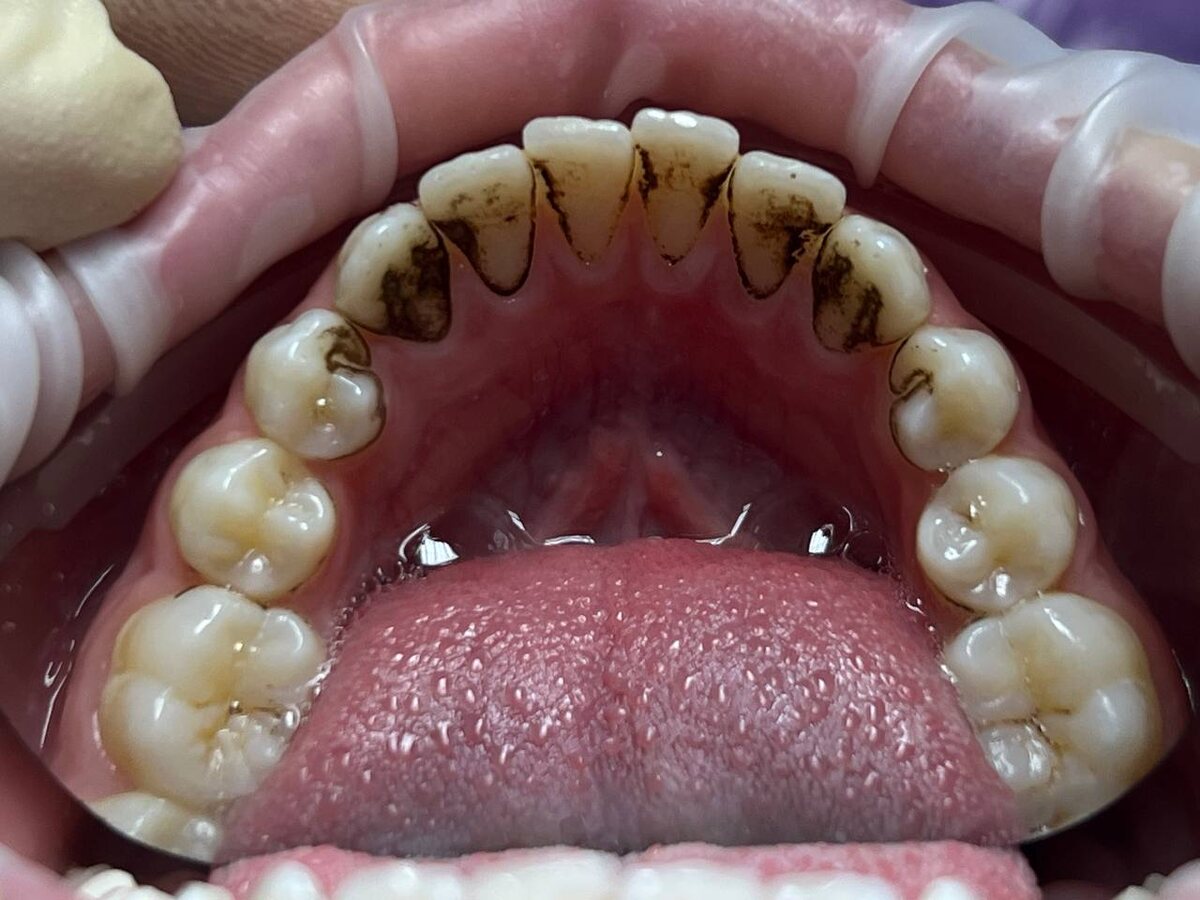

Налет Присли — это особая форма зубного налета, которая возникает у определенной группы людей, чаще всего у детей. Вот основные характеристики этого налета:

- Он имеет плотную текстуру и темный цвет — от коричневого до глубокого черного.

- Чаще всего наблюдается вдоль линии десен и на внешней поверхности зубов.

- Не удаляется при помощи обычной зубной щетки и пасты.

- Хотя зубы могут быть совершенно здоровыми, налет создает эстетический дискомфорт.